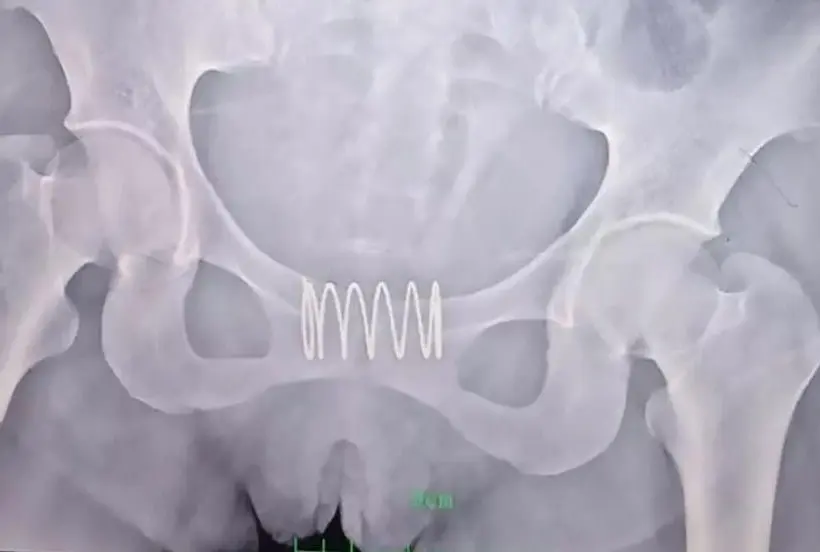

Quando os médicos foram fazer um exame ginecológico, perceberam que havia um objeto estranho na vagina da mulher. Um raio-X revelou depois que se tratava de uma mola de 5 centímetros. “O objeto já estava envolto pelo tecido vaginal”, disse a médica Fu Junhong à imprensa local.